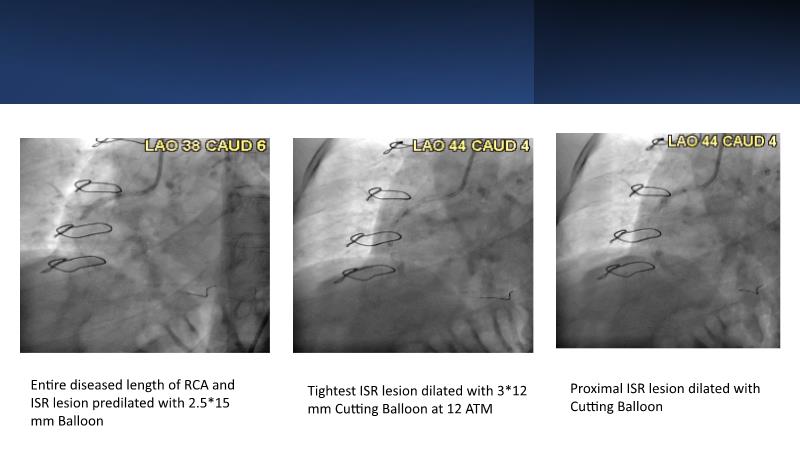

• To know why and how a fusion coating of DES+DCB stent platform is effective for the treatment of cardiovascular disease in diabetes mellitus patients via case presentations

• To understand why you can count on customised drug delivery platform of DES+DCB in complex settings with imaging-based evidence through case presentations